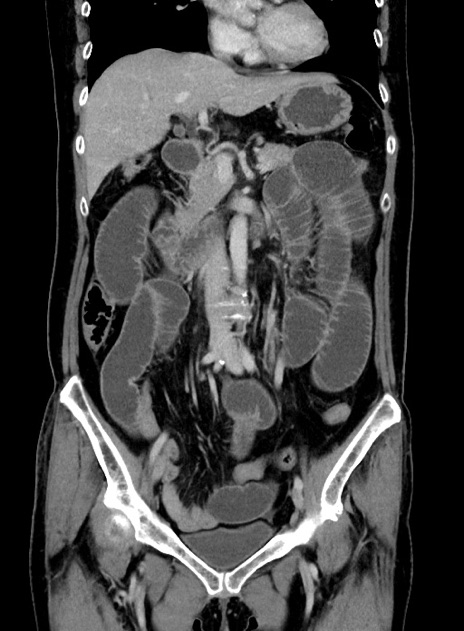

症例9(冠状断像)

【症例】 60歳代女性

【主訴】むかつき、みぞおちの痛み

【現病歴】3日前よりむかつきがあり、食事がとれない。

【既往歴】糖尿病

【身体所見】発熱なし、心窩部圧痛軽度あるも、腹膜刺激症状なし。

【データ】WBC 7400、CRP 1.92